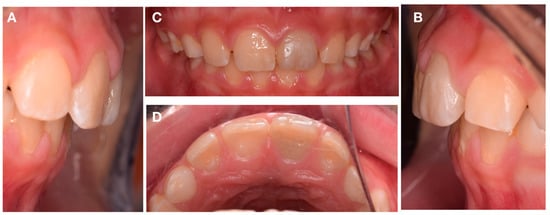

At the first visit, the canal preparation was performed after local anesthesia without vasoconstrictor (3% Mepivacaine) and rubber dam isolation. Local anesthesia was delivered because of the recent history of trauma to the soft tissues. The protocol of REP with a coronary opening with a diamond bur (Figure 3A) was initiated. The root canal system was slowly irrigated with 5.25% sodium hypochlorite (NaOCl) and then 17% liquid Ethylenediaminetetraacetic acid (EDTA) in order to remove the smear layer, being both activated with dynamic manual irrigation. The EDTA was used because of the increase in stem cells of the apical papilla survival []. The canal was then dried, Ca(OH)2 (Ultracal, Ultradent, South Jordan, UT, USA) applied as an internal medication, and then sealed with temporary restoration, being Cavit G (3M ESPE, Maplewood, MN, USA).

Figure 3.

Intra-oral photography. (A) Coronary opening. (B) Blood clot. (C) MTA placed apical to cementoenamel junction. (D) Periapical radiograph after REP procedure.

Three weeks later, on the second visit, after clinical examination, local anesthesia without a vasoconstrictor (3% Mepivacaine) was performed and the tooth was isolated with a rubber dam. Then, the pulp chamber was accessed and the removal of intracanal Ca(OH)2 (Ultracal, Ultradent, South Jordan, UT, USA) was performed by saline irrigation. Followed by drying with paper points, the revascularization procedure was performed by trespassing 2 mm beyond the apical foramen with a #25K-file (Dentsply, Maillefer, Ballaigues, Switzerland) to induce bleeding. After blood clot formation (Figure 3B), MTA (ProRoot, Dentsply, Ballaigues, Switzerland) was placed apical to the cementoenamel junction (Figure 3C) and covered with resin modified glass ionomer cement (GC International AG, Luzern, Switzerland) with the objective to seal the access (Figure 3D).

At the one-month follow-up appointment, positive sensitivity tests and negative response to percussion test were recorded. At this stage, the temporary restoration was removed, and the tooth surface was prepared for the indirect veneer with immediate dentin sealing (IDS) protocol using Optibon FL (Kerrdental, OR, USA) and Filtek Z100 (3M ESPE, Maplewood, MN, USA) on retentive areas (Figure 4A,B). Then, impressions were made using a one-step addition silicon technique Express XT and Light Body Paste (3M ESPE, Maplewood, MN, USA). on the upper arch, and in the lower arch, the impression was taken using alginate (3M ESPE, Maplewood, MN, USA).

Figure 4.

Intra-oral photography. (A) Composite veneer. (B) Veneer prep. (C) Rubber dam isolation. (D) Composite veneer immediately after cementation.

Die stone casts were made to allow for the fabrication of the indirect composite veneer with ENA HRI UD4 (Micerium, Avegno, Italy) A4 VITA-Scale (Figure 4C).

At the following appointment, the veneer adaptation was evaluated to assess marginal fit and esthetics before the adhesive procedure. Then, after rubber dam placement, the adhesion procedure was performed according to the protocol described in Table 1. After removing the glycerin gel, the marginal area was finished and polished (Figure 4D). Restoration were checked to avoid any occlusal interference.